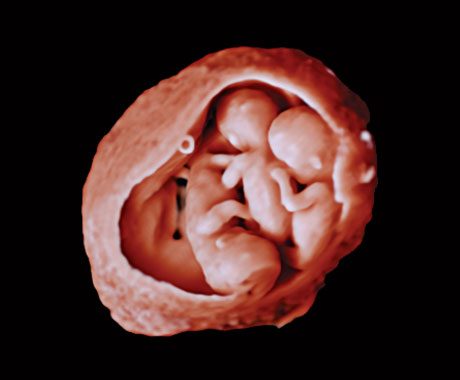

En este vídeo, el Dr. Michael Ruma presenta el transductor V9-2 para ultrasonidos 3D de Philips. El V9-2 es el primer transductor mecánico PureWave para ultrasonidos 3D de la división de ultrasonidos de Philips específico para obstetricia/ginecología y ofrece una extraordinaria calidad de imagen y un diseño ergonómico avanzado. El V9-2 está especialmente indicado para la adquisición de imágenes 2D, 3D y 4D para exploraciones obstétricas del primer, segundo y tercer trimestre..